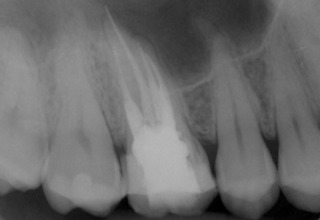

Patient N.M. wünscht eine Drittmeinung, zwischenzeitlich hatte er bereits einen zweiten Zahnarzt konsultiert. Dieser bestätigte eine insuffiziente Wurzelfüllung und vermutete eine Instrumentenfraktur im mb1 (Abb. 1).

Mittels Röntgenaufnahme lässt sich ein frakturiertes Instrument in mb1 vermuten. Des Weiteren scheint es, als sei der distale Wurzelkanal sowie der mb2 nicht abgefüllt worden, was sich zu einem späteren Zeitpunkt der Behandlung bestätigen sollte. Der Patient wurde vom vorbehandelnden Zahnarzt über die Fraktur nicht aufgeklärt.